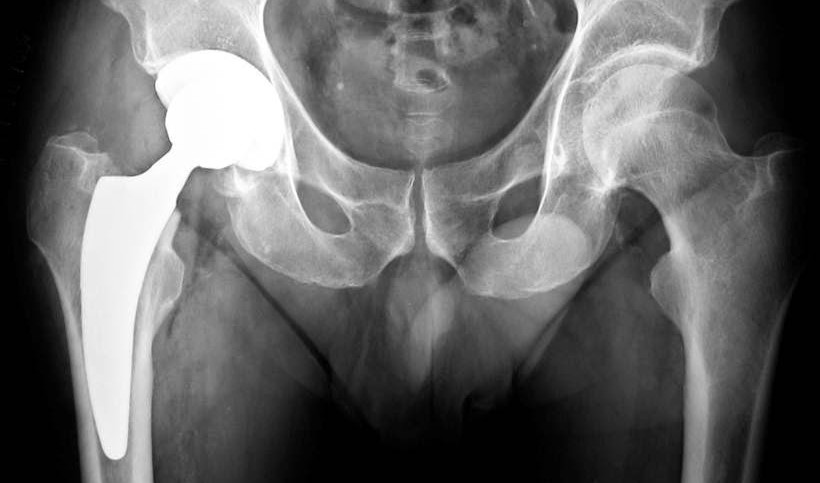

Immagine di protesi d'anca

Tecnica protesica, materiali e innovazione

“Le indagini strumentali sono importanti per identificare precocemente la causa del fallimento e programmare l’intervento chirurgico. Attualmente - precisa Antonio Capone, direttore della clinica Ortopedica e traumatologica; dipartimento Scienze chirurgiche, Università di Cagliari - l’utilizzo di moderni software di segmentazione modellazione 3D, che sfruttano le immagini derivanti dall’esame Tac, consente di rimuovere gli artefatti determinati dalle componenti protesiche metalliche e di ottenere una ricostruzione tridimensionale dei difetti ossei, fedele all’anatomia del paziente”. Il dottor Marongiu, ricercatore e segretario alla presidenza Air, rimarca un aspetto chiave: “La collaborazione con i colleghi del dipartimento di Ingegneria biomedica ci ha consentito di stampare in 3D con moderne tecnologie di manifattura additiva il segmento osseo che deve essere ricostruito per poter simulare le varie tecniche chirurgiche. Con questo processo si realizza un protocollo di trattamento specifico per il paziente (Pst) che riduce tempi chirurgici e complicanze post-operatorie. La tecnica di ricostruzione articolare prevede l'impiego di trapianti ossei, di componenti protesiche modulari o protesi custom specifiche per gravi difetti ossei”.